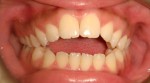

Finished Patient with a Perfect Bite and Excellent Facial Proportions